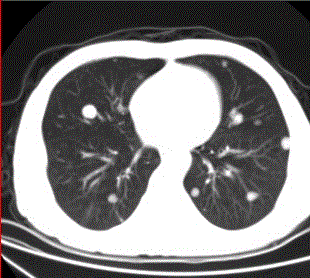

问题 患者男,45岁,因肝硬化、肝癌行肝移植术后6个月,咳嗽2周,来院复查。CR及CT影像如下图。 该例最可能的转移途径为

选项 A.经肺动脉 B.经肺动脉至淋巴管而后到肺外围 C.经纵隔淋巴结逆流到肺门淋巴结,再经肺内淋巴管到肺外周 D.经胸膜腔 E.经气道 F.经支气管动脉

答案 A

解析 A